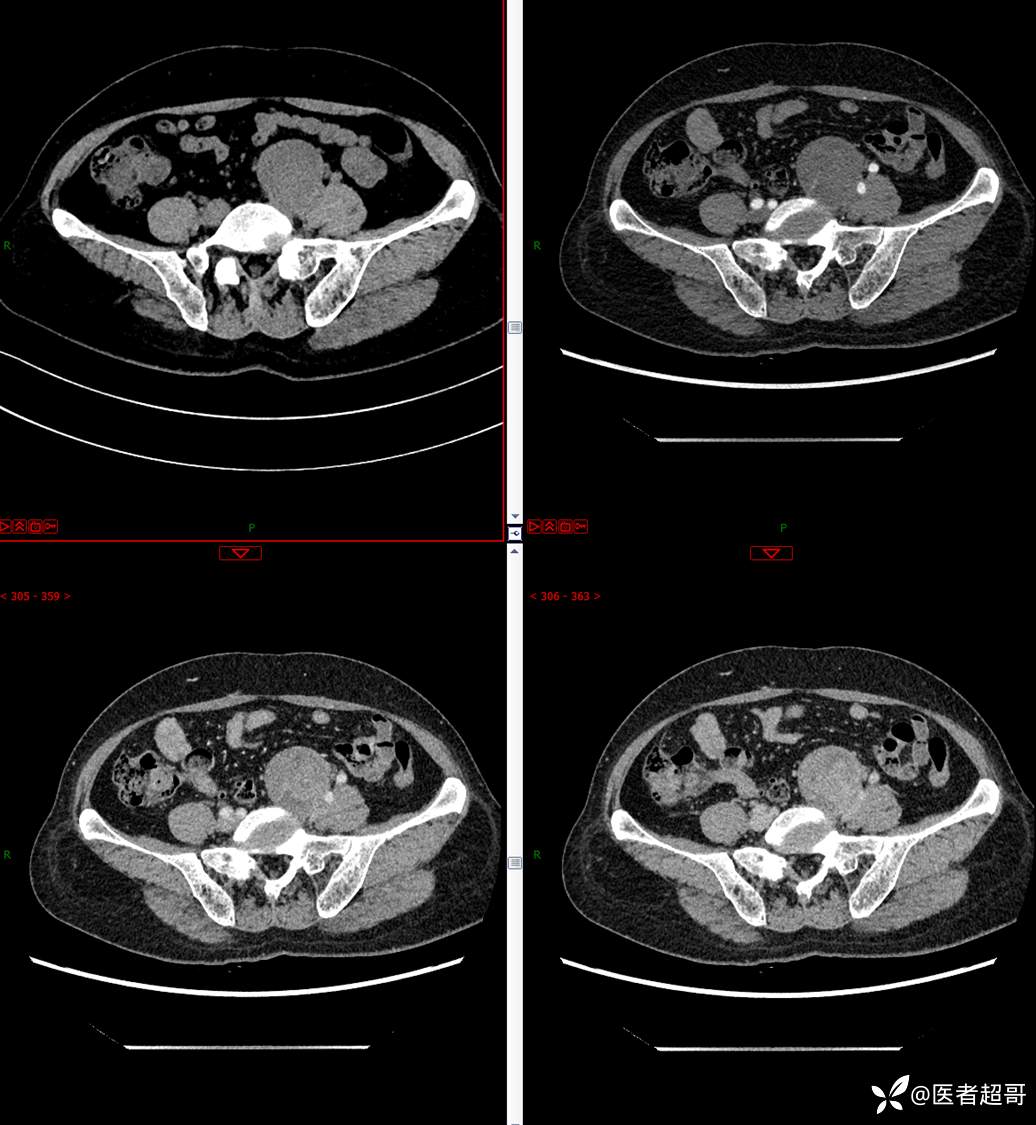

【影诊笔记559】查体发现右输尿管结石1周,发现腹膜后肿物,请分析,有病理!

•主 诉:查体发现右输尿管结石1周。

•现病史:患者1周前因小便不适来我院门诊行彩超检查提示右输尿管结石并右肾积水,伴腰疼,无血尿,无寒战,高热,患者求其进一步诊治,门诊以“右输尿管结石并右肾积水”收入院,患者自发病以来,神志清,精神可,饮食睡眠可,大便便秘,近期体重无明显增减。